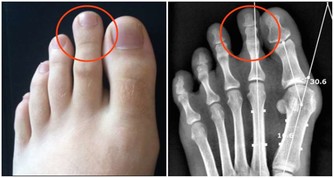

馬德龍綜合徵是一種因長期飲酒,導致脂肪代謝紊亂,在皮下等部位對稱、過度堆積而形成一種病症。脂肪常會堆積在頭部、頸部、肩部以及腰部等部位,上下肢呈現近端肥胖、遠端細小,類似動漫“大力水手”的手臂外形。